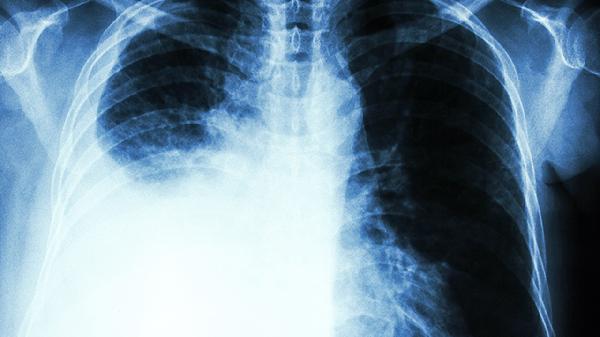

肺部炎症病变会癌变吗

5、长期慢性炎症可能通过诱导基因突变、促进细胞增殖和抑制免疫反应等机制增加肺癌风险。对于有慢性肺部炎症病史的患者,建议定期进行胸部影像学检查如CT扫描和肿瘤标志物检测,以便早期发现和治疗肺癌。